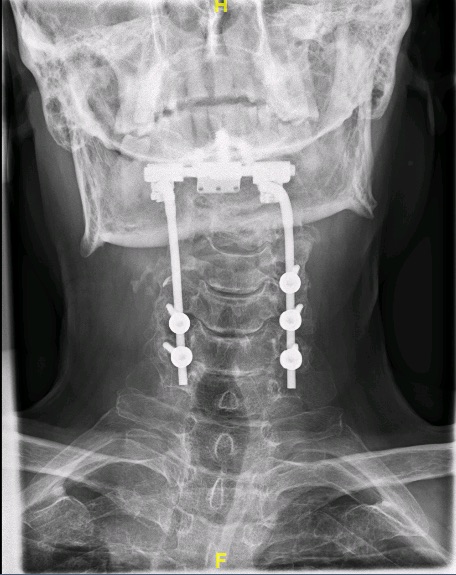

Se realizó una descompresión posterior del arco de C3 asociando una artrodesis occipitocervical. La afectación del pedículo/pars de C2 por el tumor recomendaba obviar esa vértebra en la reconstrucción.

Obsérvese afectación pedículo/pars C2 por el tumor